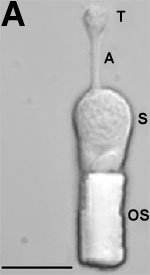

A: Enzymatically dissociated salamander rod photoreceptors possess intact rhodopsin-containing outer segment (OS), soma (S), axon (A), and presynaptic terminals (T). The scale bar represents 10 μm. B: Representative current responses from intact dissociated salamander rods resulting from a 2 s depolarizing voltage step from -60 mV to 0 mV were recorded from the same salamander rod photoreceptor before (1), during (2), and after washout (3) of a test puff of medium containing 50 μM fluoxetine hydrochloride, 10 μM fluoxetine hydrochloride, or drug vehicle (DMSO) only. Traces shown for each concentration of fluoxetine were recorded from different cells. Note the virtual elimination of both the ICl(Ca) tail current and outward currents by 50 μM fluoxetine. A test puff of 10 μM fluoxetine results in less significant changes in the initial amplitude of both outward and ICl(Ca) tail currents but significantly shortens the duration of the sustained ICl(Ca) tail current. DMSO alone did not alter the control currents. C: Statistical comparison of ICl(Ca) tail currents and outward currents measured in the presence of a 50 μM fluoxetine test puff (n=9) or a 10 μM fluoxetine test puff (n=5) with currents measured from the same cells in control bath solution. The control currents for each cell were defined as 1 for normalization purposes. Also shown is a comparison of the duration of ICl(Ca) tail currents measured in the presence of a 10 μM fluoxetine test puff with those measured from the same cells in control bath solution. The control duration for each cell was defined as 1 for normalization purposes.